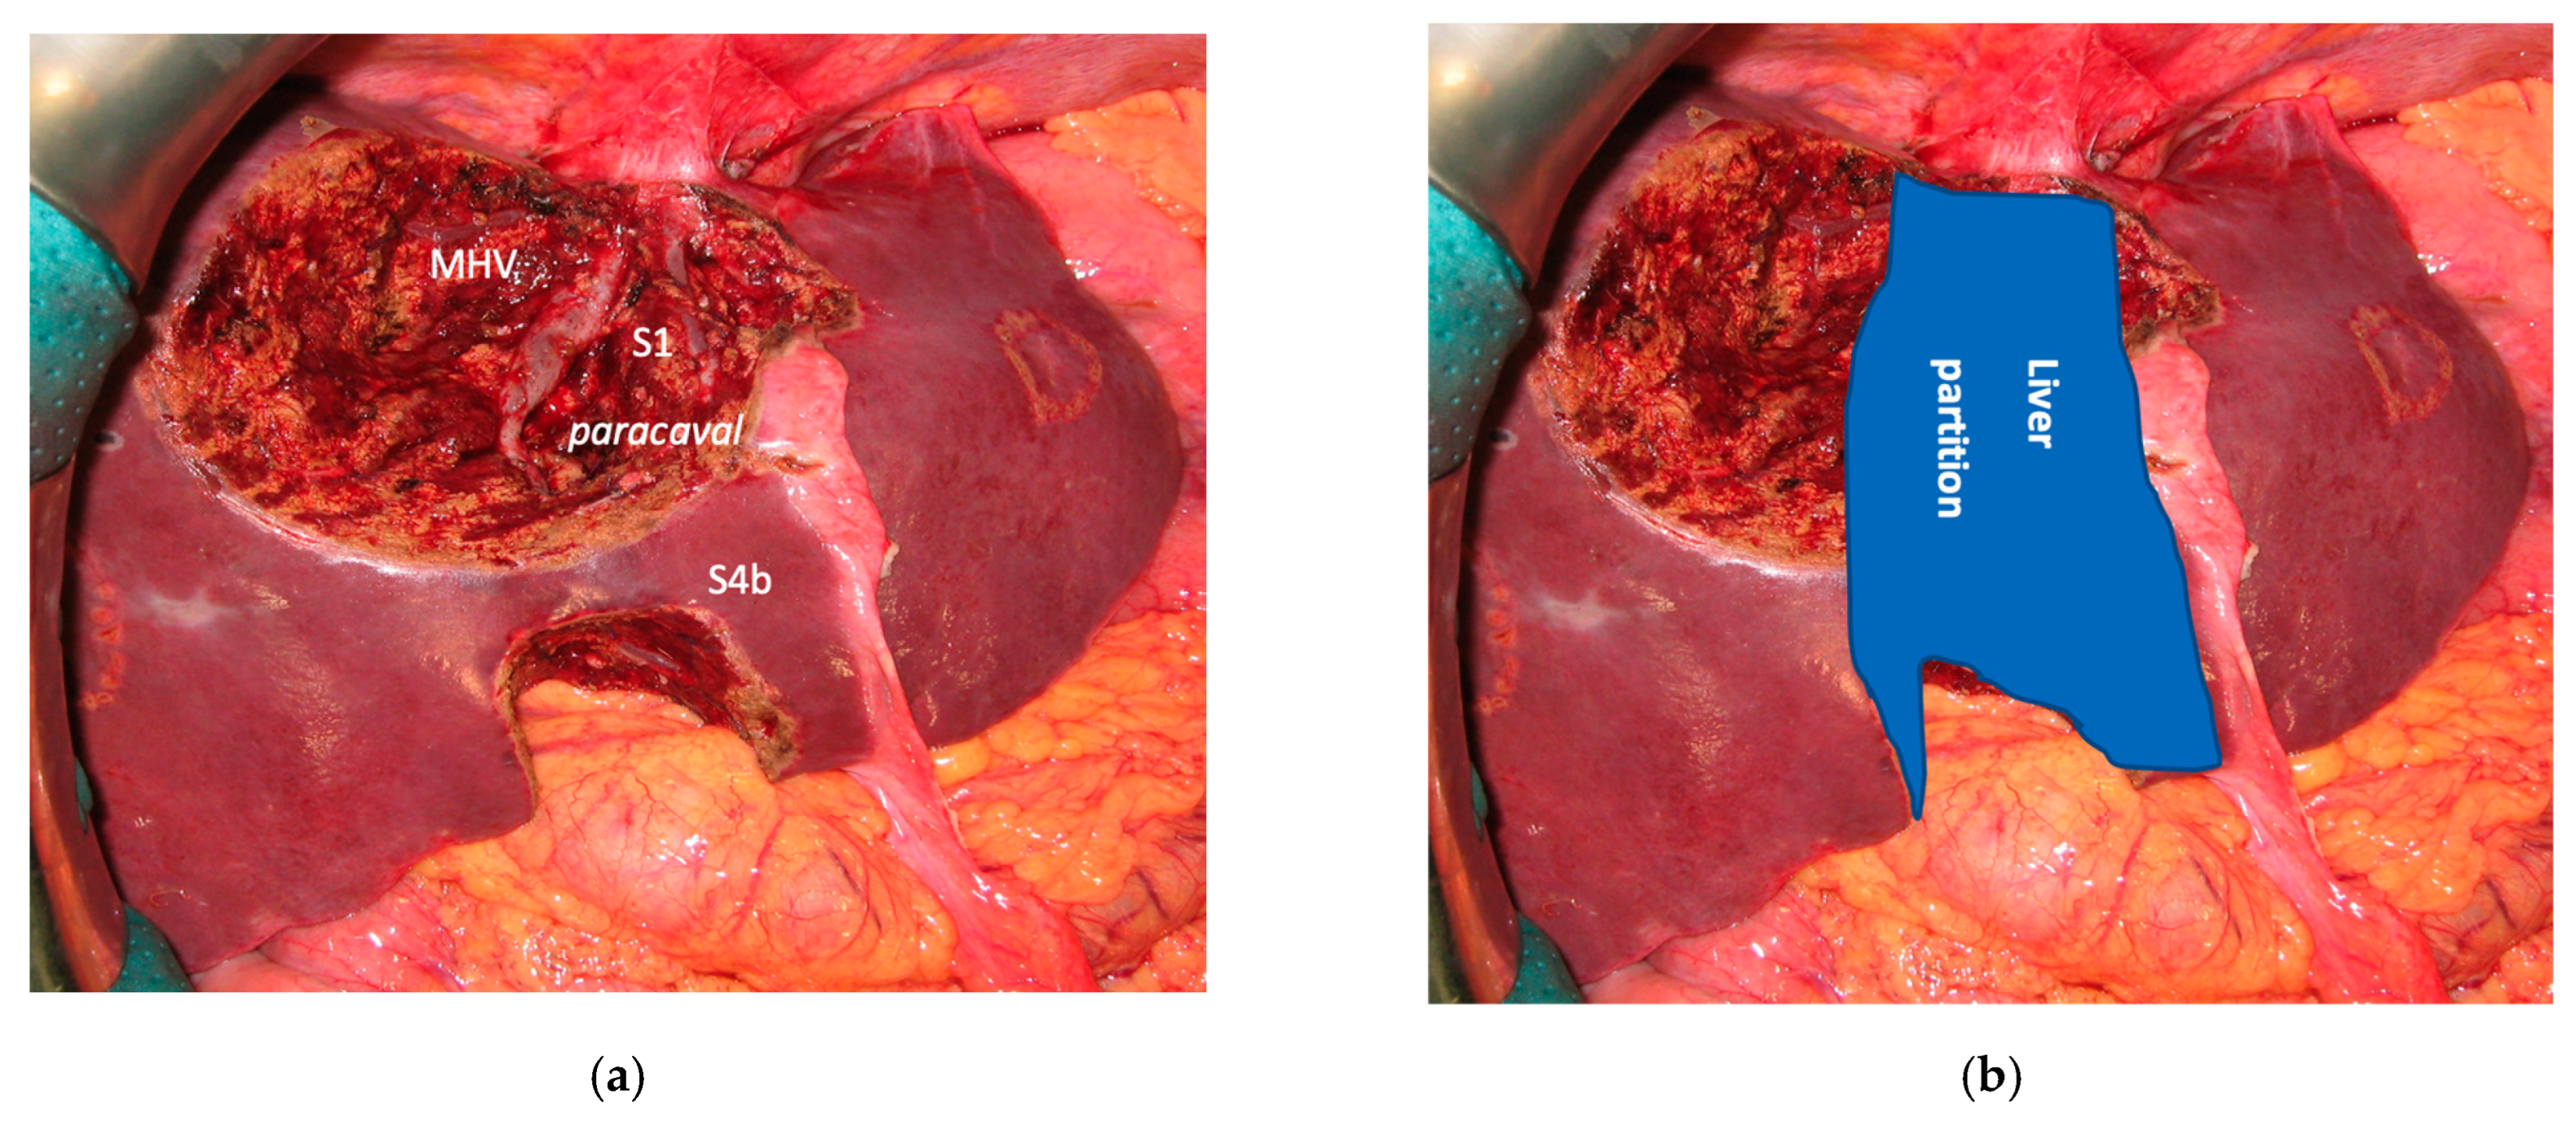

3.1. MLP

In all 15 cases planned vessel-guided MLP was successfully carried out. For the surgical approach, a J-shaped laparotomy was used in 13 cases and the xipho-pubic incision in two; no thoraco-abdominal incision was needed. In two cases of MLP performed as the first stage of ALPPS, liver partition was obtained with a single transection line: in one case (FLR = S2/S3/S4b) between a part of S4b and S5 since S4a/S1 were resected in previous e-OSH, in the other case (FLR = S4/S2/Spiegel lobe) the single transection line preserved part of S4a/S4b and the Spiegel lobe. In 11 cases liver partition was obtained with a minor mesohepatectomy: in one case with resection of S4a/S1 partially extended to S5 preserving S4b, in two cases with resection of S1/S4 preserving the Spiegel lobe, in one case with resection of segments S5/S8 extended to the caudate processus of S1 preserving the Spiegel lobe and paracaval portion of S1 and in the other seven cases with anatomic resection of S1/S4 (see Figure 4).

Liver partition was obtained with a major mesohepatectomy in two cases with anatomical resection of S1/S4/S8 (en-bloc with biliary tree in one, see Figure 5).

Figure 4. Intraoperative field images of a vessel-guided mesohepatectomy of S1/S4 en-bloc with MHV for liver partition (MLP). MLP is a minor resection (less than 3 adjacent liver segments) inducing a major hepatic scaffold modification transforming the liver into a paired organ. (a) Liver transection lines (yellow dotted lines). (b) Intraoperative view of the two livers. (c) Surgical specimen of S4/S1 en-bloc with MHV corresponding to a volume of 205 mL. Abbreviations: MLP: mesohepatectomy for liver partition; MHV: middle hepatic vein; RHV: right hepatic vein; S: segment; GP: glissonean pedicle; UP: umbilical portion.